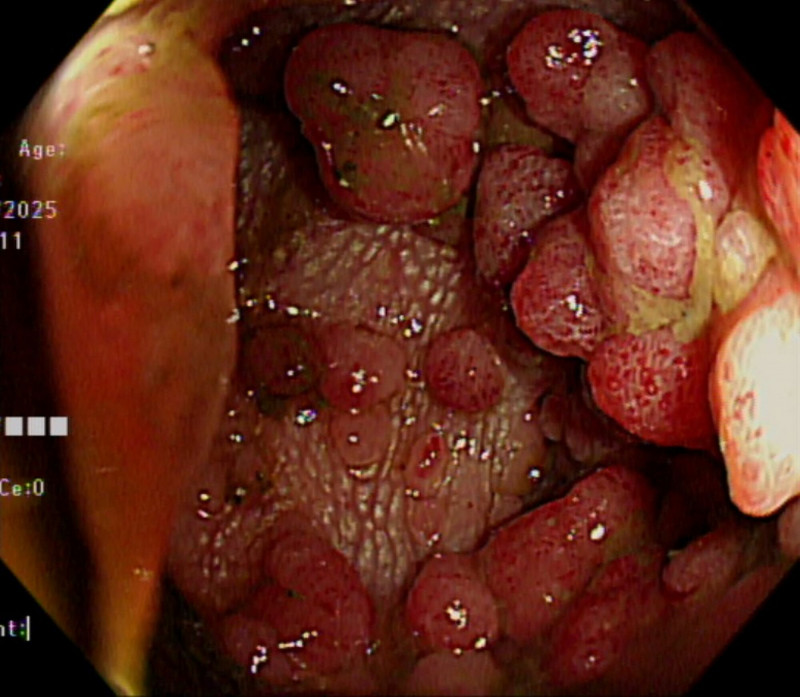

罕見FAP 腸道長滿瘜肉恐癌化!預防性全大腸切除

〔記者丁偉杰/嘉義報導〕家族性腺瘤性瘜肉症(Familial Adenomatous Polyposis,簡稱FAP)是一種罕見但極具危險性的遺傳疾病,若未及早診斷與治療,幾乎百分之百會演變為大腸直腸癌。嘉義基督教醫院最近為多名患者預防性全大腸切除術,目前恢復良好,醫師提醒,家族中若有人年輕時就罹患大腸癌或出現大量瘜肉恐癌化,其他成員必須提高警覺。

另一名40歲男子大腸內出現數百顆大小不一的瘜肉,因腸阻塞送嘉基急診,檢查發現降結腸瘜肉癌變,又罹患十二指腸壺腹癌及肝癌,經3次手術與多科團隊合作,最終成功清除病灶。

嘉基大腸直腸外科主任朱峻廷醫師表示,FAP為顯性遺傳,只要父母任一方帶有突變基因,下一代就有50%機率遺傳。患者多在青少年時期就開始出現大腸瘜肉,30歲左右腸道可能布滿上百或上千顆。若未治療,90%以上會在中年以前癌化,「只要活得夠久,終其一生幾乎百分之百會變成大腸癌」。